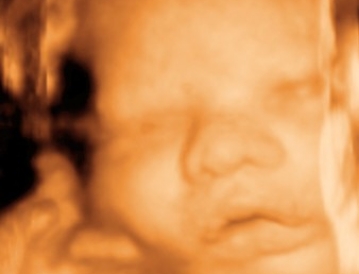

FOTOGRAFÍAS

Cara 1